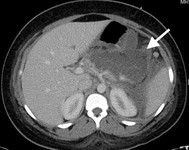

CT scan of teenage girl presenting with mid-epigastric abdominal pain as a result of gallstone pancreatitis. The large fluid collection in the pancreatic bed (white arrow) and lack of pancreatic enhancement suggest liquefactive necrosis of the pancreas

From the collection of Dr Kuojen Tsao; used with permission